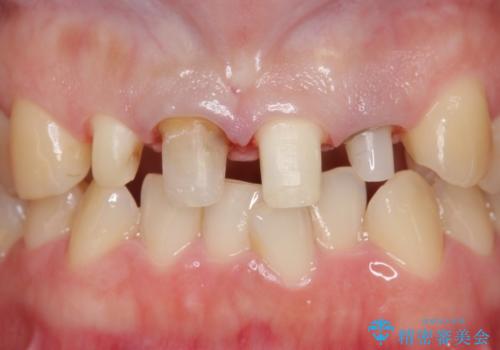

- 前歯の色や長さ、歯茎との隙間の金属が気になるのでセラミックで治療したいといらっしゃった方の症例です。

見た目改善のため、前歯4本をオールセラミッククラウン(スペシャル)で補綴しました。

右上1と左上2は再根管治療を行っております。

- オールセラミッククラウン…¥130,000×4、仮歯…¥10,000×4、ファイバーコア…¥20,000×2、精密根管治療費別途費用は治療当時の料金となります